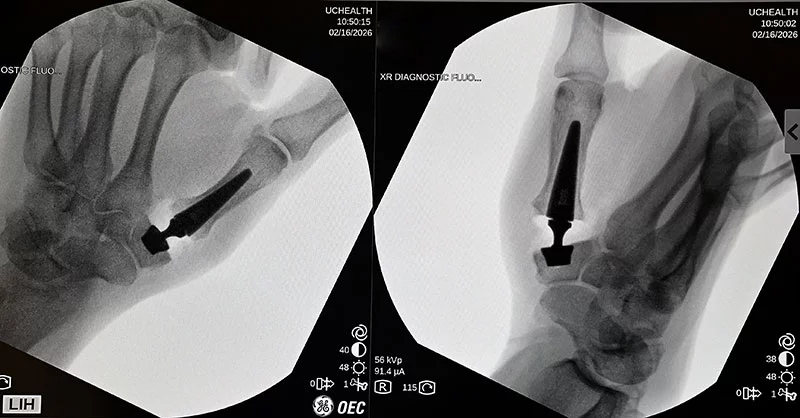

Dr. Fraser Leversedge, chief of hand surgery at UCHealth University of Colorado Hospital, rotates the patient's hand for an X-ray during a new thumb arthritis surgery now offered at UCHealth. The surgeons took X-rays throughout the procedure to ensure correct placement of the implant. Photo by Sonya Doctorian, UCHealth.

Dr. Fraser Leversedge, chief of hand surgery at UCHealth University of Colorado Hospital, rotates the patient’s hand for an X-ray during a new thumb arthritis surgery now offered at UCHealth. The surgeons took X-rays throughout the procedure to ensure the correct placement of the implant. Photo by Sonya Doctorian, UCHealth.

X-rays of the implant after final placement during a new thumb arthritis surgery. The first patient in Colorado and in the western U.S. received a new type of thumb prosthesis on Feb. 16 at UCHealth University of Colorado Hospital. Thumb arthritis is quite common. Hand surgeons from UCHealth and the University of Colorado Anschutz School of Medicine traveled to Europe to learn the new technique that should boost function and reduce recovery times and pain for patients. Photo by Sonya Doctorian, UCHealth.